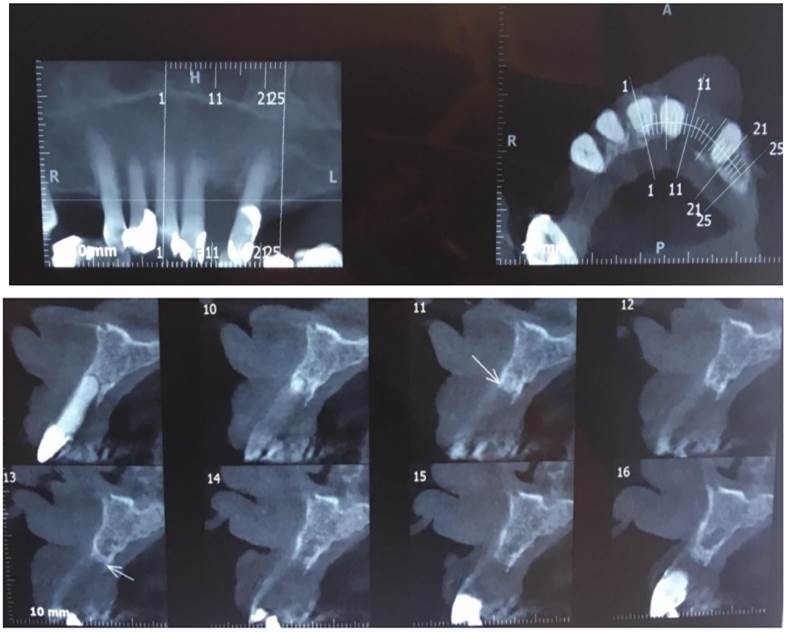

Se plantea como primera hipótesis diagnóstica una lesión inflamatoria reactiva, posible granuloma periférico a células gigantes. Se solicita imagen de tomografía computada para valorar el hueso subyacente, presencia o no de reabsorción ósea o de lesión central. La imagen muestra ausencia de pieza 2.2, enfermedad periodontal crónica, sin alteraciones óseas en el hueso asociado a la lesión a biopsiar (Fig. 3).

Por los antecedentes médicos personales se plantea como diagnóstico diferencial una metástasis renal.

Se solicita a la paciente que concurra a la próxima consulta con informe histopatológico de la nefrectomía realizada y coordinar para la semana siguiente la biopsia incisional de la lesión oral. En esta segunda consulta, clínicamente se constata en la lesión un aumento de volumen considerable (Figs. 4 y 5). El resultado histopatológico de la nefrectomía realizada fue de carcinoma renal de células claras.

A causa de la velocidad de crecimiento constatada en una semana y el diagnóstico de la lesión renal previa, se plantea, previo a la biopsia, un diagnóstico presuntivo de metástasis renal.